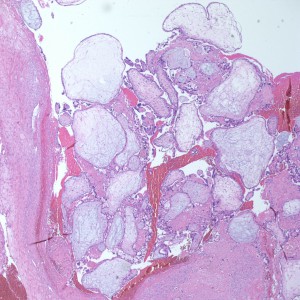

Gross: Received are multiple fragments of red-brown soft tissue (23.0 x 14.0 x 4.4cm) in maximum dimensions. Chorionic villi but no fetal tissue are identified. Non-clot areas were entirely submitted.Images:

Diagnosis: Complete Hydatidiform Mole

At low power we see throughout the specimen that numerous enlarged hydropic chorionic villi are present (circles).